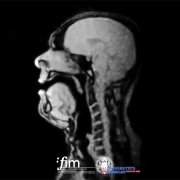

Su Cosa succede nel cranio di un cantante d'opera durante un concerto?